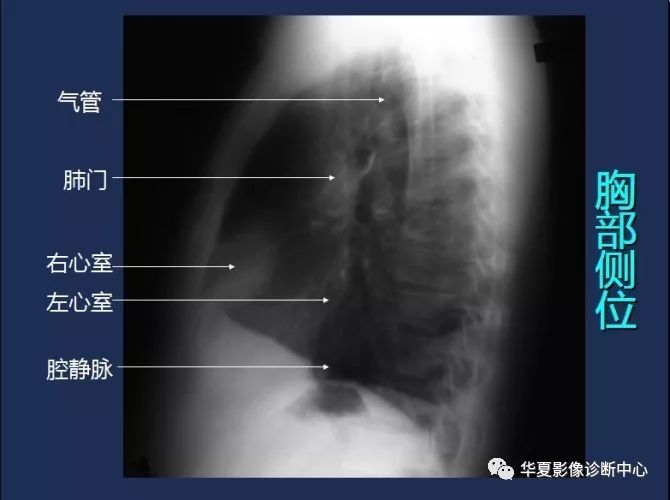

胸部侧位 医学百科网 | YxBaike.Com